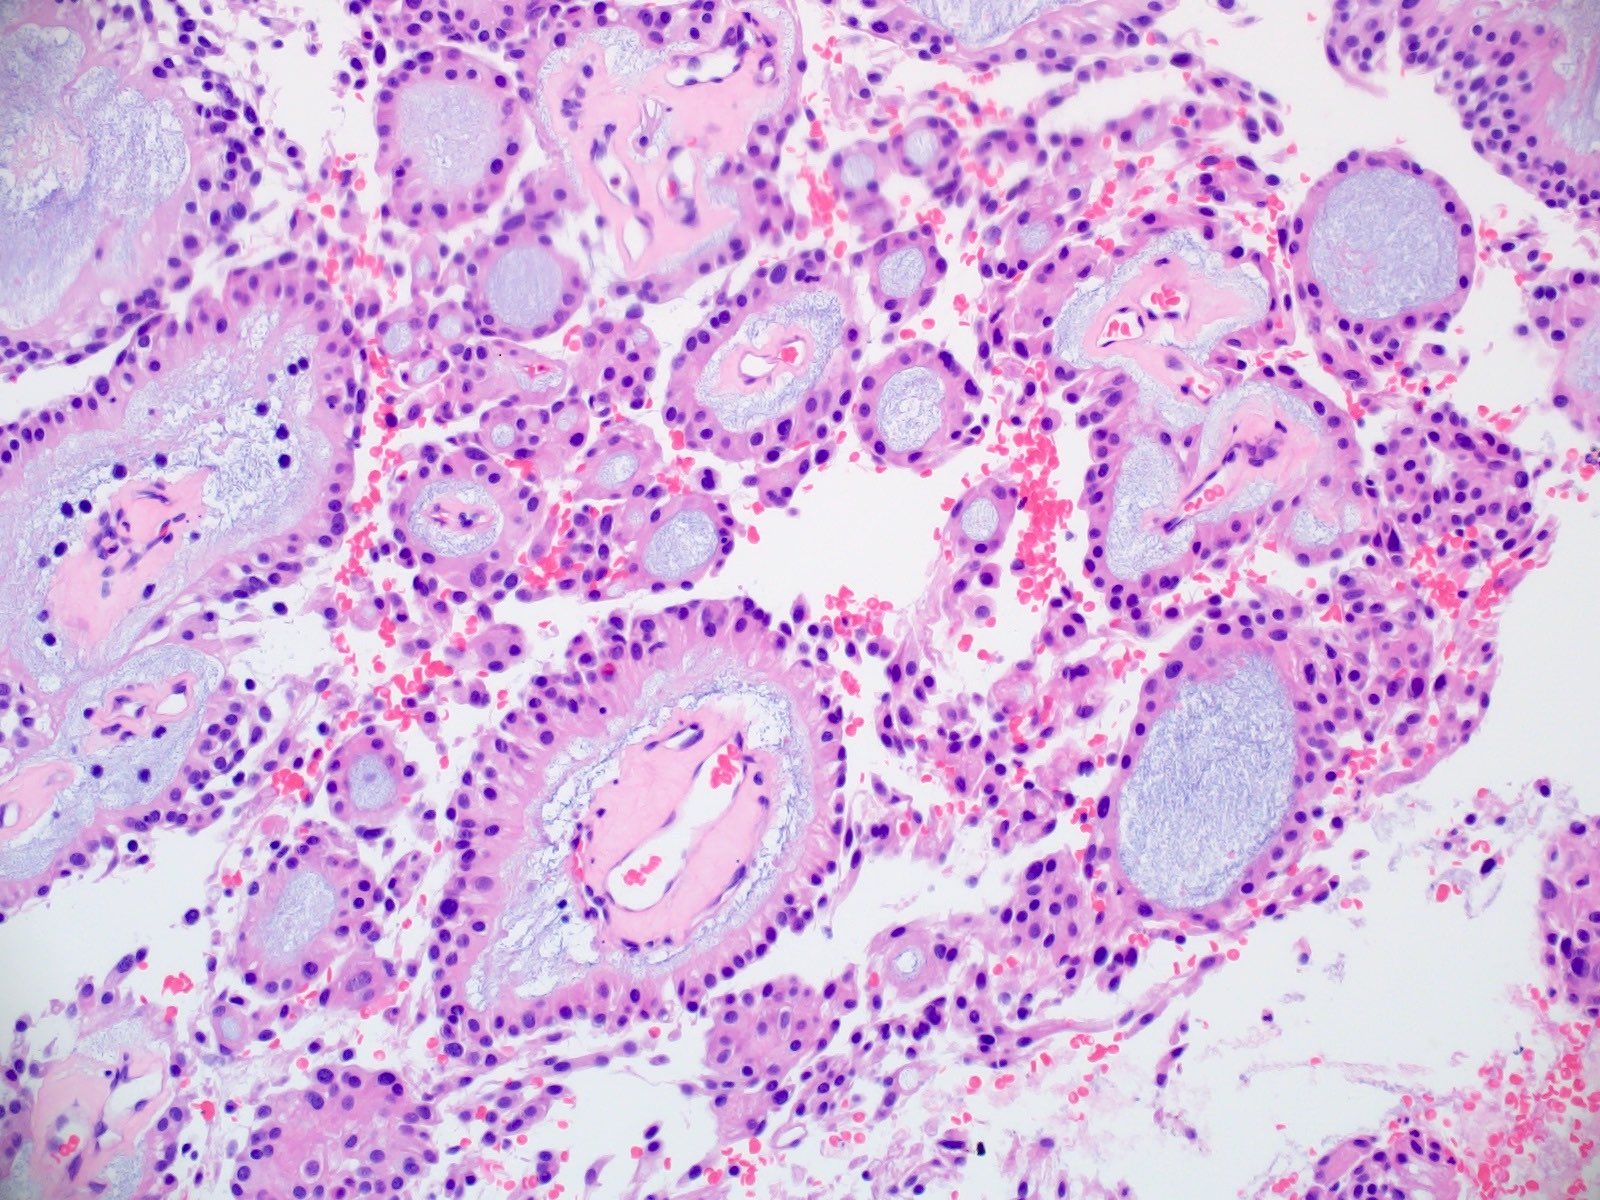

Microscopic (histologic) description

- Most common pattern is radial arrangement of cuboidal to epithelioid elongated glial tumor cells around hyalinized fibrovascular (central, often hyalinized blood vessels) cores in a papillary configuration

- Accumulation of basophilic myxoid material around blood vessels (myxoid stroma) and in microcysts

- Myxoid material is highlighted by PAS and Alcian blue positive staining

- In cases composed of confluent sheets of epithelioid cells with little or no papillary structures, PAS and Alcian blue positivity is useful in reaching a correct diagnosis

- Fascicular growth and spindle cells are common

- Pleomorphic tumor giant cells can be seen

- Occasionally tumor cells show distinctive eosinophilic balloons; these are PAS positive spherules that demonstrate spiculated reticulin staining (Am J Surg Pathol 1996;20:1091)

- Uncommon examples reported as anaplastic myxopapillary ependymomas show hypercellularity and reduced mucin in association with at least 2 of the following features: ≥ 5 mitoses / 10 high power field, Ki67 labeling index ≥ 10%, microvascular proliferation, spontaneous necrosis (Brain Pathol 2019;29:75)

Microscopic (histologic) images